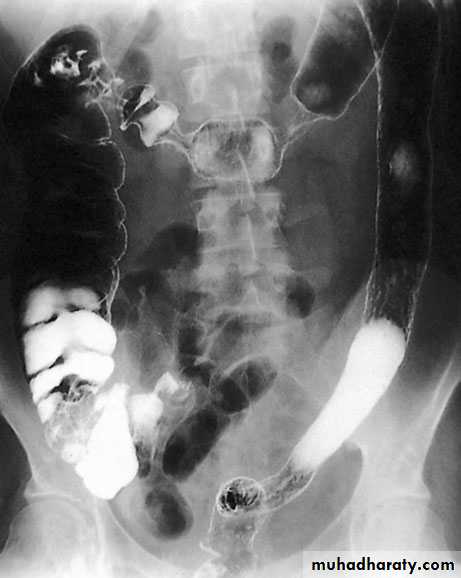

ImagingBarium enema will show similar features to those of colonoscopyin the colon. The best investigation of the small intestine is smallbowel enema . This will show up areas of delay anddilatation. The involved areas tend to be narrowed, irregular and,sometimes, when a length of terminal ileum is involved, theremay be the string sign of Kantor. Sinograms are useful in patientswith enterocutaneous fistulae. CT scans are used in patients withfistulae and those with intra-abdominal abscesses and complexinvolvement .Magnetic resonance imaging (MRI) has been shown to be usefulin assessing perianal disease.